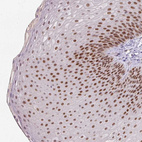

Immunohistochemical staining of human skin shows strong nuclear positivity in squamous epithelial cells.